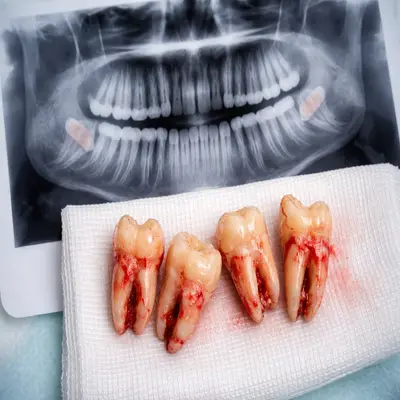

دندانهای عقل خارجشده با ریشه کامل کنار تصویر رادیوگرافی OPG